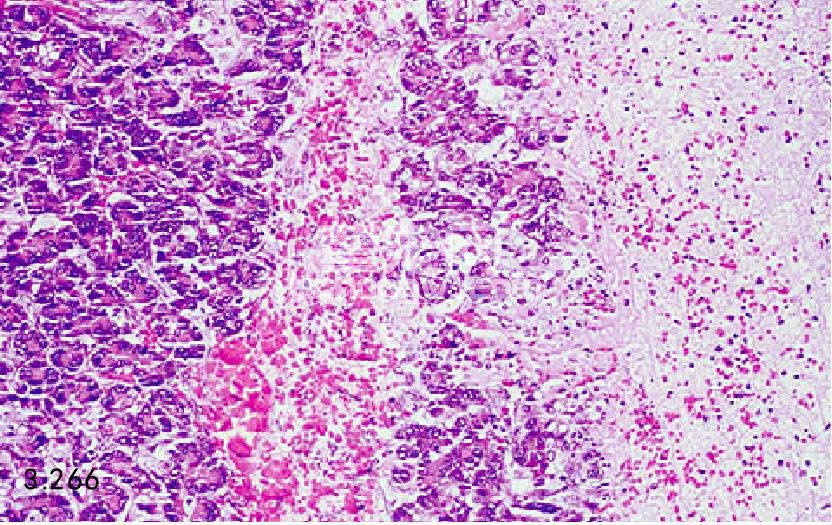

图3.265和图3.266 上图患犬胰腺的组织病理学图片显示为腺体坏死、出血、水肿,由中性粒细胞和巨嗜细胞的炎性浸润(H&E)。